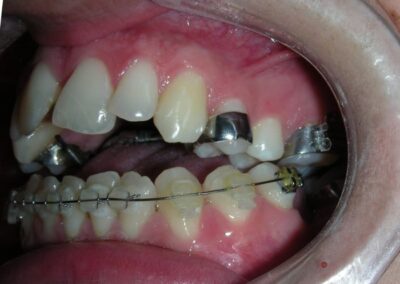

After two years of treatment using appropriate biomechanics, the overbite was successfully corrected from -8 mm to +1 mm, achieving complete closure of the anterior open bite without exacerbating the patient’s lower facial third vertical proportions. At this stage, occlusal contacts were verified using articulating paper, and functional movements of the canines and incisors were evaluated to ensure proper anterior guidance and disclusion patterns. The patient was then referred to speech therapy (myofunctional evaluation) as part of the pre-debond assessment protocol.

Finishing and Retention

At the completion of treatment (28 months) , the patient exhibited significant skeletal and dental improvements consistent with the initial treatment objectives. A reduction of 3 degrees in lower anterior facial height and a 4-degree increase in the facial axis angle were observed on post-treatment cephalometric analysis, indicating a favorable counterclockwise, anterior mandibular rotation. This skeletal change, in conjunction with the mesialization of posterior segments and space closure mechanics, led to the successful resolution of the anterior open bite. During the retention phase, a modified Hawley appliance was used in the maxillary arch, while the mandibular arch was stabilized with a fixed retainer made of twist-flex (supercable) wire #33 to #43 , which had been heat-treated to eliminate its elasticity. This retention strategy was complemented with myofunctional therapy, aimed at ensuring long-term neuromuscular stability.

The use of cephalometric measurements as quantitative indicators of skeletal and dental movement validated the biomechanical plan established from the outset of treatment. Although the patient maintains a dolichofacial biotype, the desired functional outcome—including anterior occlusal contact, vertical control, and stable mandibular positioning—was effectively achieved.